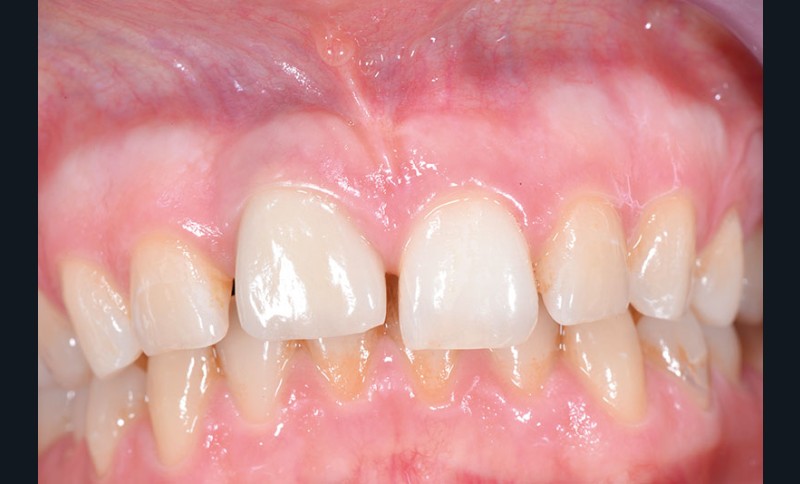

Une patiente âgée de 28 ans consulte pour un problème esthétique au niveau de la dent 11, porteuse d’une couronne implanto-portée (fig. 1a).

L’examen clinique révèle une différence d’alignement et un tissu gingival péri-implantaire peu épais sur cette couronne implanto-portée.